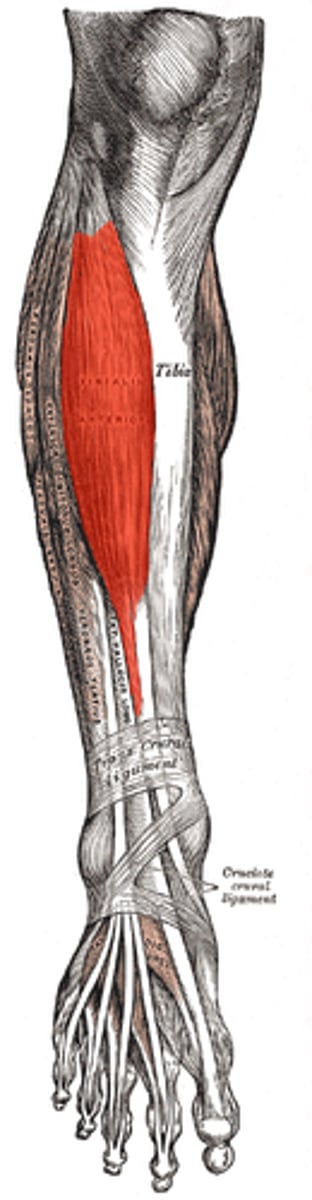

tibialis anterior

dorsiflexes and inverts foot